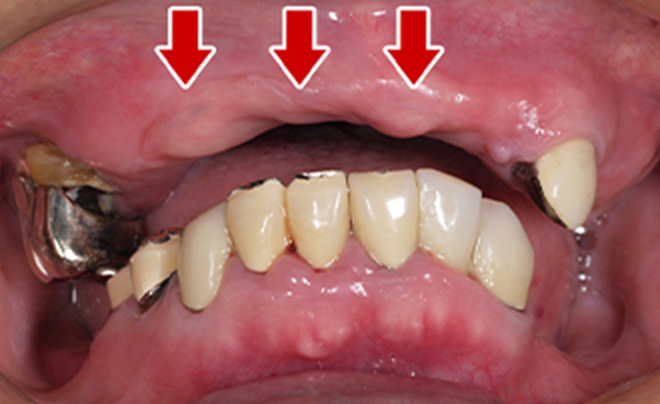

Before

After

| 68歳 男性 | 紹介 |

|---|---|

| 主訴 | れ歯が合わない 食べにくい 人生を豊かにしたい |

| 処置内容 |

上顎4本で12歯(オールオン4)、下顎4本5歯 上下抜歯即時埋入、即時荷重(手術当日にインプラントの上に仮歯装着) |

| 治療費用 | 上顎: 約220万(税込) 下顎: 約180万円(税込) |

| 治療期間 | 上顎: 9ヶ月 下顎: 6ヶ月 |

| リスク |

術後の腫れ、痛み(ピークは3日後、1週間で軽減) 上部構造物、仮歯の破折、人工歯根脱落リスクがあります |